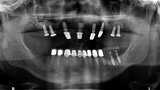

Fig. 29: OPG prior to treatment.